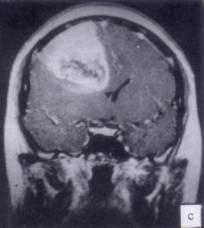

问题 病历摘要:??患者男性,52岁。头痛伴呕吐2月,呕吐呈喷射性。既往身体健康。体检:神清,表情淡漠,反应迟钝,双眼底视神经乳头明显水肿,左鼻唇沟稍浅,左腹壁反射减弱,左上下肢肌力4级,左Babinski征(-)。 为明确诊断,可申请哪些辅助检查?

选项 A.内分泌功能检查 B.脑电图 C.头颅平片 D.头颅MR E.TCD F.SPECT G.CT H.PET

答案 DG